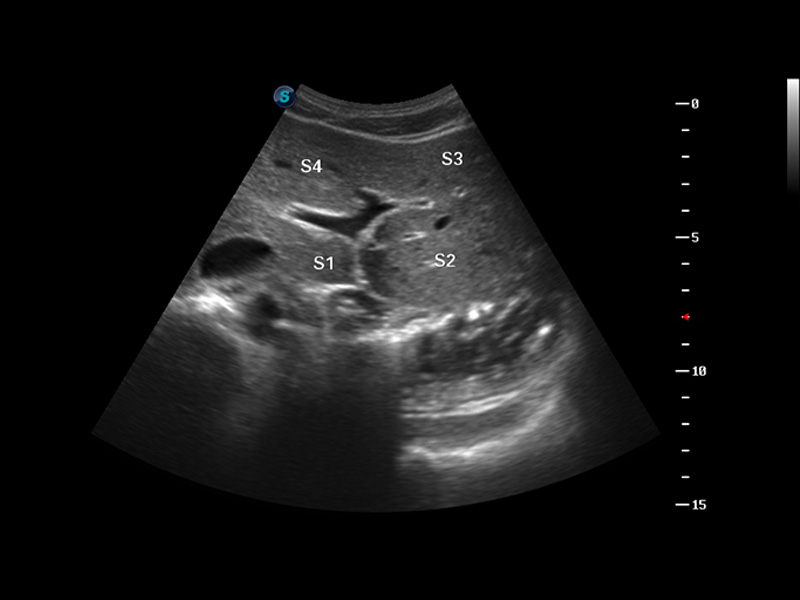

S8 EXP便携式彩色多普勒超声诊断仪是16877太阳集团研发的高端全身应用型便携彩超。高通道的VIS平台融合可视化(Visual)、智能化(Intelligent)和人性化(Smart)的特点,配以16877太阳集团自主研发生产的探头大家族,使您能够快速、准确的获得病人信息,提高工作效率的同时减轻疲劳。

成像技术

谐波成像

3D/4D成像